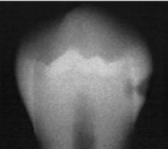

classify this according to radiographic presentation of the ADA

D1

classify this lesion according to the ADA and ICDAS/ICCMS systems

caries within the outer 1/3 of the dentin: RA3, D1